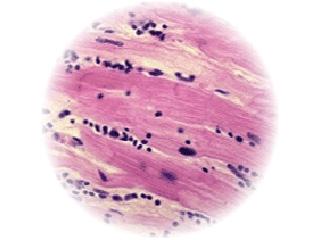

Myocarditis is an inflammatory disorder of the myocardium with necrosis of the myocytes and associated inflammatory infiltrate. It is usually caused by infection with a virus, particularly adenovirus or enterovirus (e.g., Coxsackievirus). These viruses typically cause other less serious diseases, such as gastrointestinal problems and the common cold. Although the utility of myocardial biopsy is debated, suspected myocarditis can be classified based on pathologic findings as defined in the Dallas or Marburg Criteria.

- Myocarditis: Myocardial necrosis, degeneration, or both, in the absence of significant coronary artery disease with adjacent inflammatory infiltrate with or without fibrosis

Acute (active) myocarditis: A clear-cut infiltrate (diffuse, focal or confluent) of >14 leukocytes/mm² (preferably activated T-cells). The amount of the infiltrate should be quantitated by immunohistochemistry. Necrosis or degeneration are compulsory, fibrosis may be absent or present and should be graded.